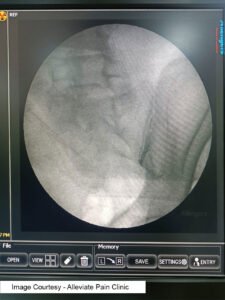

Fluoroscopy guided Sacroiliac Joint Injection of Corticosteroid + Local AnestheticIntra-articular steroid injections involve the direct injection of corticosteroids into the sacroiliac joint, aiming to reduce inflammation and alleviate pain. This procedure is often guided by fluoroscopy or ultrasound to ensure accurate placement of the medication. Studies, such as the one published in the “American Journal of Physical Medicine & Rehabilitation,” have shown the effectiveness of intra-articular steroid injections in providing short to medium-term relief for sacroiliac joint pain (Erdine et al., 2004).